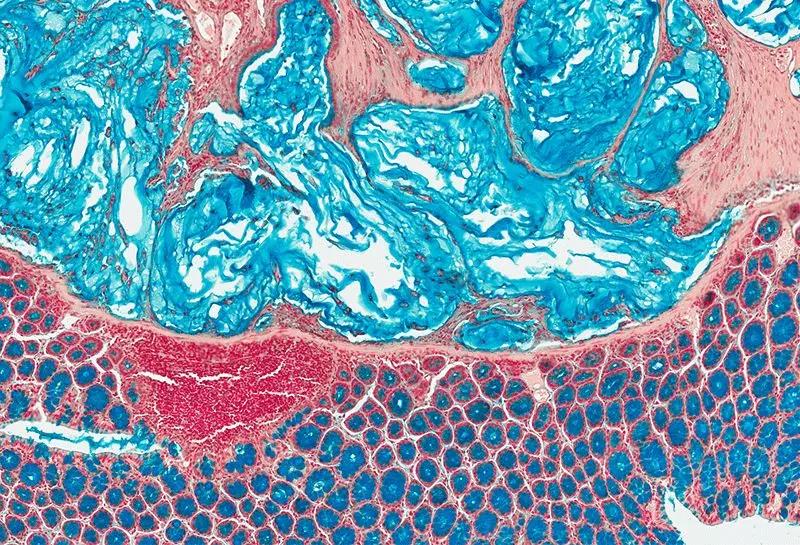

“内放疗”是一种放射性粒子植入术。医生利用现代影像学技术将具有放射性核素的粒子直接插植到肿瘤病灶内或肿瘤周围,放射性粒子通过持续释放射线对肿瘤细胞进行杀伤。“内放疗”属于高度适形放疗的一种,目前国内所应用的放射性粒子主要指碘125粒子。8Wz帝国网站管理系统

碘125粒子发出γ射线,该射线可以破坏肿瘤细胞核的DNA双链,导致DNA分子链的单链断裂或双键断裂,使肿瘤细胞失去繁殖能力; 射线还可以使机体内的水分子电离,产生自由基,该自由基与生物大分子相互作用,引起组织细胞的损伤,持续照射肿瘤细胞,使肿瘤的氧增比减少、乏氧细胞比例减少,不断地消耗肿瘤干细胞而使肿瘤细胞死亡。